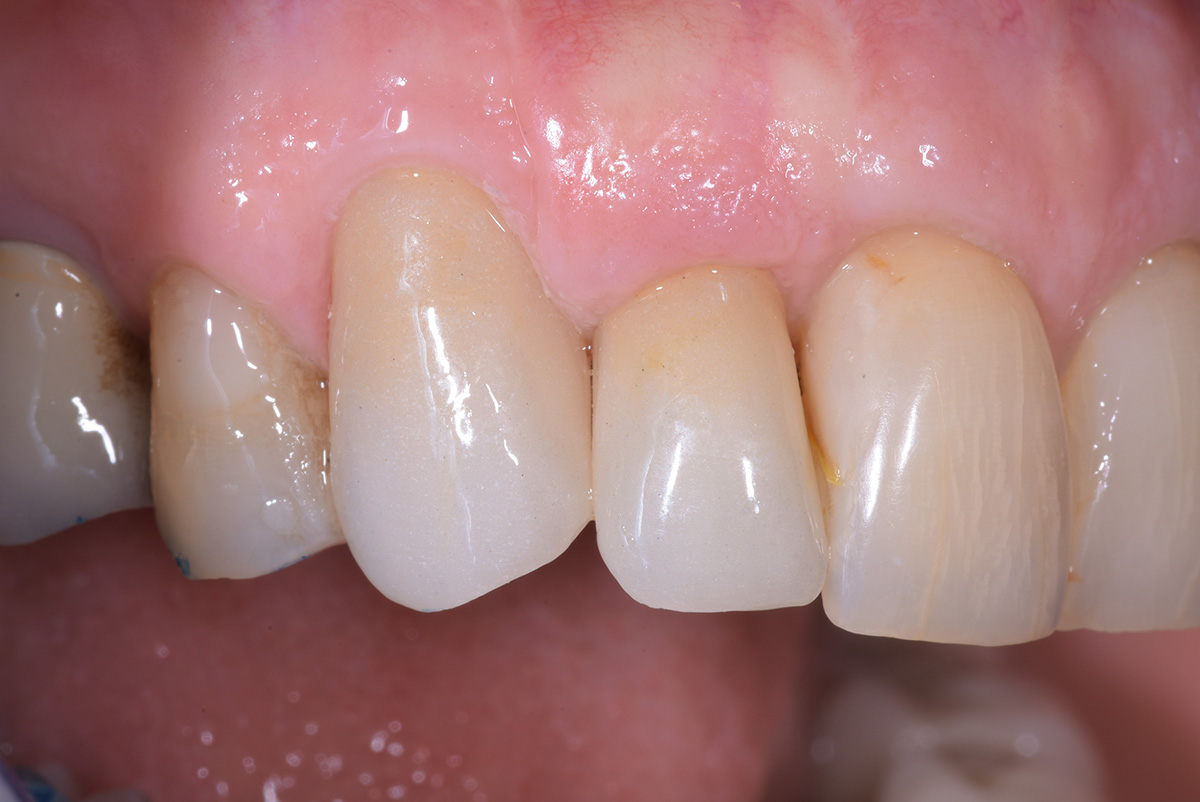

Correzione estetica mucogengivale, mediante innesto di connettivo, di esposizione impianto di incisivo laterale sup dx, con rifacimento protesico di laterale e canino.